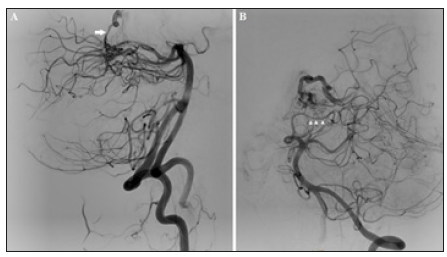

Figure 2:Diagnostic angiography: AP left vertebral arteriogram. (A) Arterial phase: showing multiple pontine perforators feeding the AVM; arising mainly from the most proximal long circumflex branch. (B) Early venous phase: showing two draining veins; the most tortuous of them is the lateral mesencephalic vein. Both of them are drained by the left basal vein of Rosenthal.